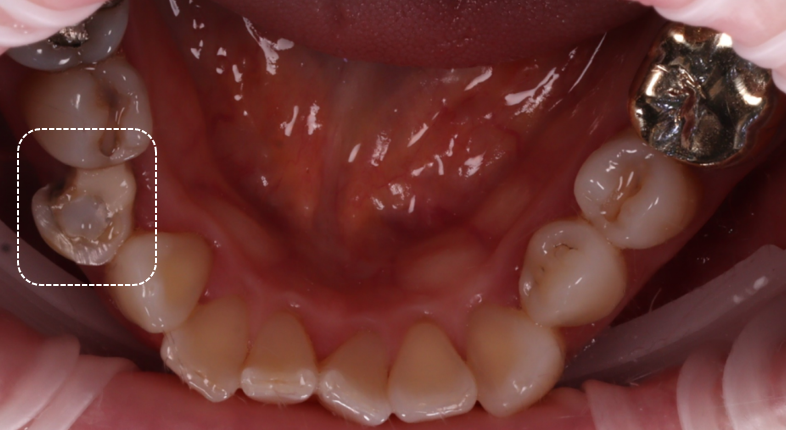

그리고 오른쪽 아래 작은 어금니는 신경치료가 된 상태였고, 크라운이 되지 않은 상태였습니다.

촬영일 : 251230

① 우선 잇몸을 짓누르고 있던 기존의 레진 덩어리를 모두 조심스럽게 제거하기로 했습니다.

② 그리고 염증 때문에 퉁퉁 부어오른 잇몸을 레이저로 깔끔하게 다듬는 치은 절제술을 병행하기로 했죠. 이렇게 해야 치료 후에 양치질과 치실로 깨끗하게 관리할 수 있는 '길'이 만들어지거든요.

③ 마지막으로 주변 치아와 완벽하게 어우러지는 색상의 심미 레진 비니어로 디자인하고 어금니 부위는 레진으로 코어를 만든 후 강도가 높고 정교한 지르코니아 크라운으로 보강하여 치아의 기능을 회복시키기로 했어요.